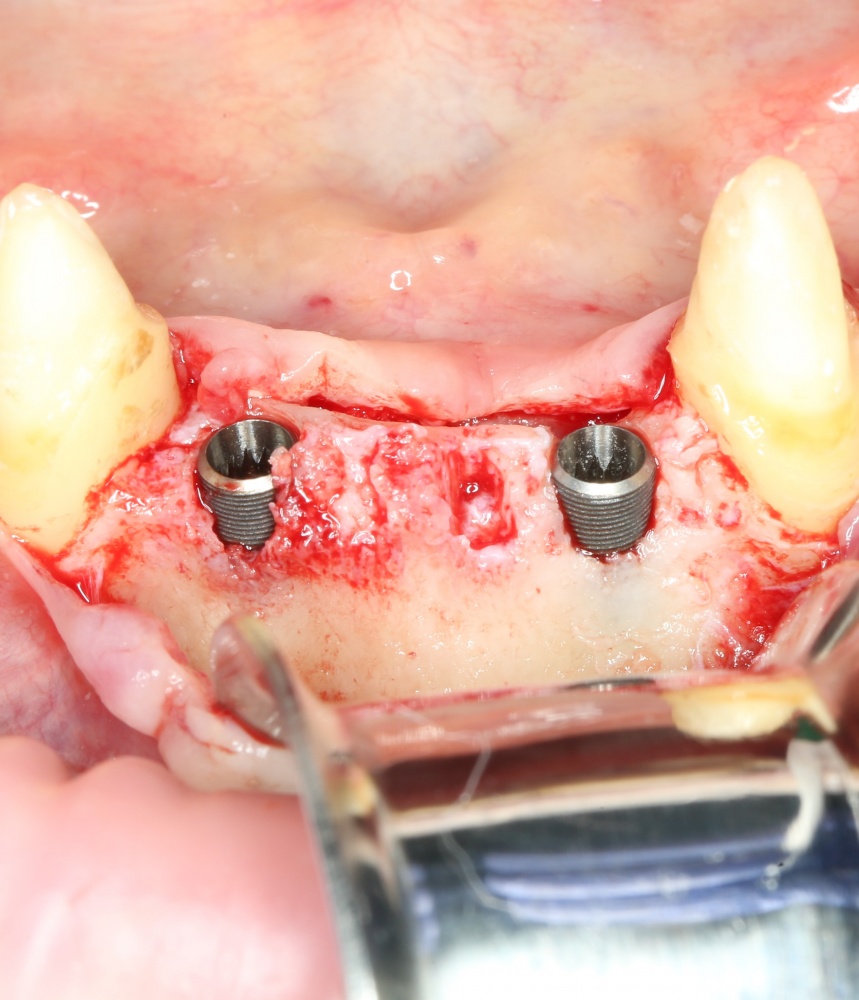

Рекомендации по установке имплантов. Для всех. Часть V.